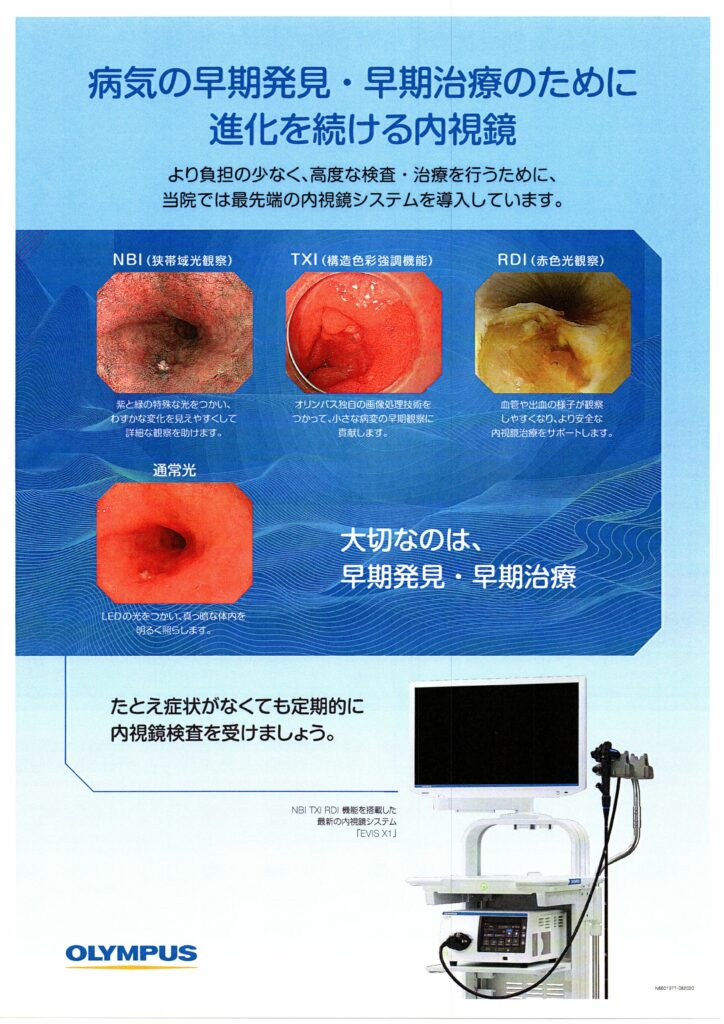

2020年10月1日より内視鏡センターに名古屋市内初導入の内視鏡システムが導入されました。

・オリンパス EVIS X1 2台

狭帯域光観察:NBI(Narrow Band Imaging)BLI(Blue LASER Imaging)

このシステムでは、狭帯域化された2つの波長の光を用いることにより、発見が困難な病変を見つけたり、がんの範囲の詳細な診断をすることが可能です。 特に、食道がんや咽頭、喉頭のがんはNBIで観察することで、発見の精度が上がります。